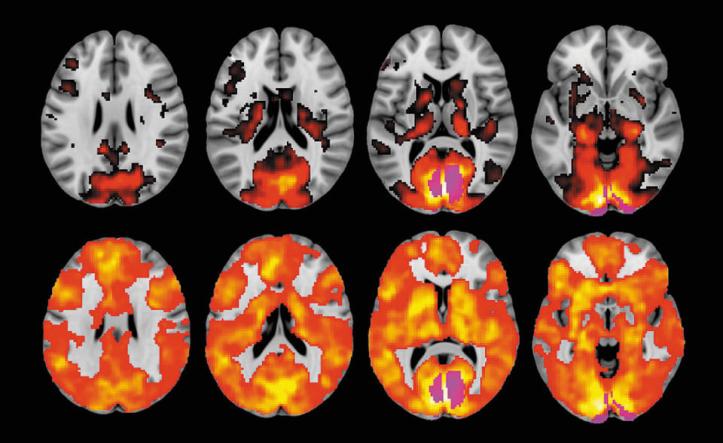

The drug also seems to connect previously isolated parts of the brain. Scans from Carhart-Harris’s research, conducted with the Beckley Foundation in Oxford, show a riot of colour in the volunteers’ brains, compared with those who have taken a placebo. The volunteers who had taken LSD did not just process those images they had actually seen in their visual cortexes; instead many other parts of the brain started processing visions, as though the subject was seeing things with their eyes shut. “The brain becomes more globally interconnected,” says Carhart-Harris. The drug, by acting on the serotonin receptor, seems to increase the excitability of the cortex; the result is that the brain becomes far “more open”.

All lit up These four cross-sections of a brain show that, under LSD

Photo by: row two